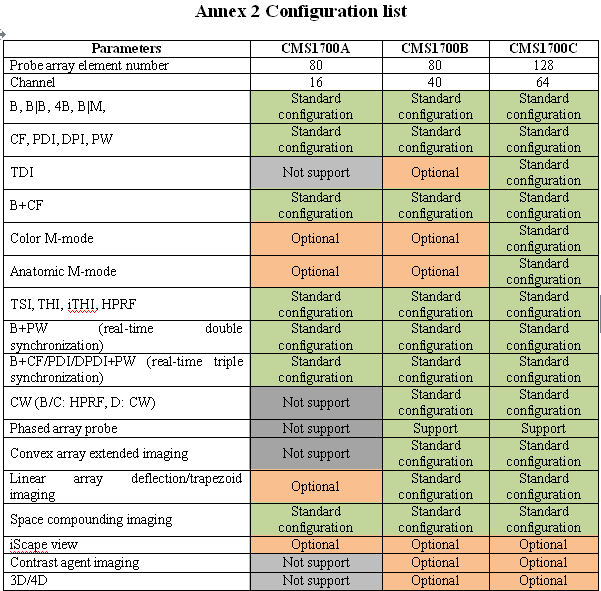

Additionally, the device includes Power Doppler functionality, which enhances the ability to detect blood flow and other internal processes. This technology provides more detailed imaging, allowing for better patient assessment and treatment planning. The Doppler ultrasound functionality ensures that even the smallest anomalies can be detected with clarity and precision.

The user interface of the Laptop Color Doppler Ultrasound is designed for ease of use. It features a high-resolution display, intuitive controls, and customizable settings. This makes it accessible for both new and experienced Sonographers. The device runs on powerful software that supports various diagnostic applications, ensuring versatility in its use. Therefore, it can be used for a wide range of procedures, from obstetric exams to cardiac assessments.